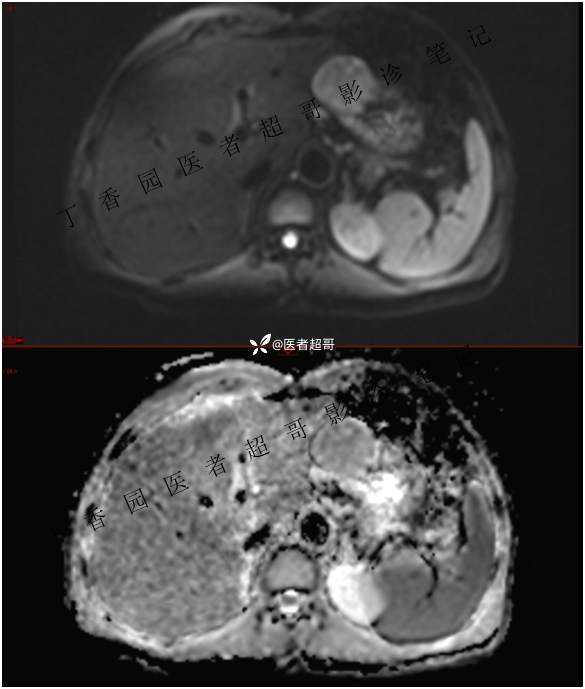

肝胃间隙肿瘤,间质瘤?平滑肌瘤?还是鞘瘤?有结果,请分析!

现病史:患者于3天前查体行肝胆脾胰肾彩超示肝内实性占位,无恶心、呕吐,无发热、寒战,无腹胀、腹泻,进一步于医院行上腹部CT增强示:肝胃交界处肿块。未行特殊治疗。今患者为求进一步治疗,来我院就诊,门诊以“肝占位性病变”收入院。患者自发病以来,神志清,精神可,饮食睡眠可,二便可,体重近期未见明显变化。